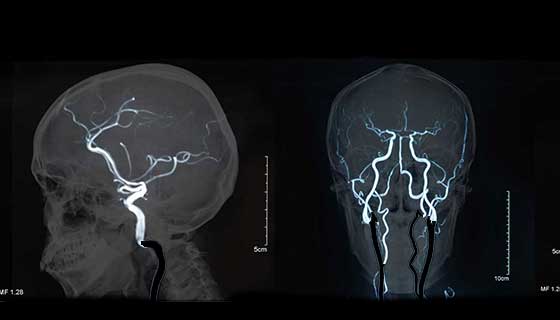

脑动脉瘤是脑动脉上的异常膨出部分,是发生蛛网膜下腔出血的常见原因。脑动脉瘤好发于组成脑底动脉环的大动脉分叉或分支的远侧角处,很少发生于脑动脉的周围支上。发生率较高者为前交通脑动脉瘤(25%~28%),其次为后交通脑动脉瘤(25%),再次为大脑中脑动脉瘤(13.4%~19. 8%)。发生于椎-基底动脉系统者约占5%~8%。

脑动脉瘤的瘤体一般较小,在破裂时其直径通常在0.6~1.0cm左右,超过2.5cm者即称为较大脑动脉瘤。脑动脉瘤一般为单发,多发性脑动脉瘤约占20%,其中以双脑动脉瘤较多见。